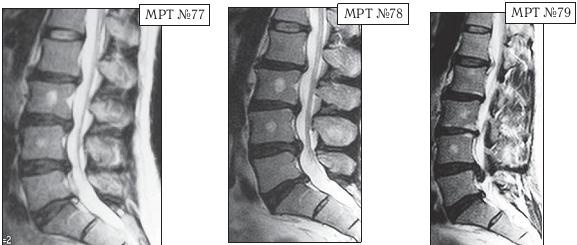

В январе 2002 года пациенту сделали МРТ (№ 77). Мануальный терапевт, проводивший данное лечение, ознакомившись с результатами обследования, объяснил, что в связи с наличием протрузий и грыжи межпозвонковых дисков дальнейшее применение мануальной терапии противопоказано, а также противопоказаны вытяжение позвоночника, йога, интенсивные нагрузки и т. д. В общем-то дал рекомендации, на удивление, довольно грамотные. Только непонятно в таком случае, почему он до лечения не провёл диагностическое обследование пациента и почему продолжал применять мануальную терапию после явного ухудшения состояния пациента?!

На MPT № 77 от 2002 года, наблюдается выраженный дегенеративно-дистрофический процесс, осложнённый протрузиями в сегментах LII—LIII, LII—LIv, LV—SI и грыжей межпозвонкового диска в сегменте LIv-Lv.

На МРТ № 78 от 2007 года отмечается прогрессирование дегенеративного процесса, снижение высоты межпозвонковых дисков, увеличение грыжи межпозвонкового диска в сегменте LIv-Lv.

На МРТ № 79 от 2010 года наблюдается дальнейшее прогрессирование дегенерации и образование секвестрированной грыжи межпозвонкового диска с каудальной миграцией секвестра в сегменте LIv-Lv

После медикаментозного лечения в стационаре самочувствие пациента улучшилось. В дальнейшем, по мере необходимости, он подлечивался амбулаторно и два раза лежал в стационаре. После очередного обострения в 2007 году сделали МРТ (№ 78), на котором наблюдалось прогрессирование дегенеративного процесса, но довольно умеренное. Новый год (2010) данный пациент встречал в кругу друзей, где уже другой друг расхвалил ему ещё одного специалиста в области мануальной терапии, который за два сеанса «поднял» его жену. Четвёртого января прошёл один сеанс у этого «специалиста». По словам пациента, ему «стало легче». Пятого января он прошёл ещё сеанс у данного специалиста. Вначале было «легко, хорошо», но вечером того же дня почувствовал боли. Утром встать уже не смог.

Сделали МРТ (№ 79), диагностировали секвестрированную грыжу межпозвонкового диска в сегменте LIV-LV. Надеюсь, что вы, уважаемый читатель, уже сами понимаете, что применение мануальной терапии в качестве лечения данной патологии было серьёзной ошибкой, которая привела к значительным осложнениям. Но тем не менее, этот случай очень показателен в плане адаптативных механизмов и компенсаторных возможностей организма и того, что происходит в случае их срыва. Всё-таки с 2002 года по 2007 дегенерация развивалась под «контролем» и если бы не «друзья» с их «медвежьей услугой», то возможно не было бы таких последствий.

В чём причина в данном случае резкого образования секвестрированной грыжи межпозвонкового диска? Основная причина таится в срыве адаптивных механизмов. Дегенерация в межпозвонковых дисках развивается как бы по спирали, где на каждом её витке срабатывают защитные (адаптивные) механизмы. Организм постепенно включает данные механизмы, которые «тормозят» и берут под контроль этот процесс. Затем подключаются компенсаторные механизмы. Так происходит адаптация и компенсация, постепенно приспосабливающая организм уже к новым условиям существования. Однако когда происходит срыв адаптивных механизмов (мануальная терапия, вытяжение и т. д.), влекущий за собой нарушение компенсаторных возможностей организма, то дегенерация развивается уже не по спирали, а по прямой — происходит её стремительное, бесконтрольное и неуправляемое развитие.